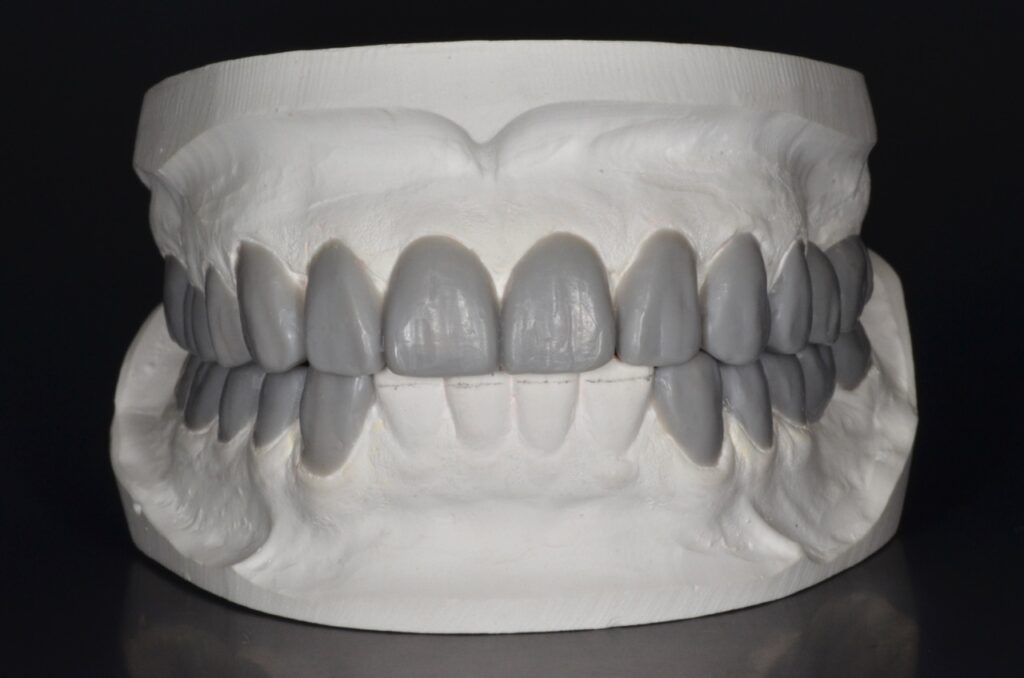

治療計画を練る上で、歯型を模型にして噛み合わせの器械(咬合器)上に患者様の状態を再現します。レントゲンやCT、写真を参考にし歯科用ワックスで治療のゴールをシミュレーションします。